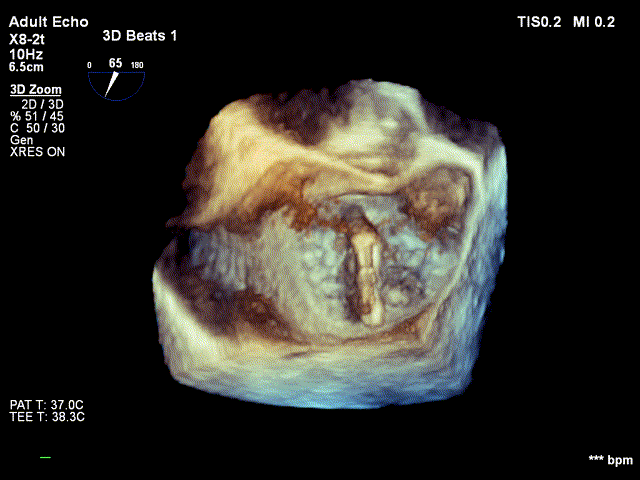

术前超声

捕获瓣叶,进行夹合 3D切面调整位置及钟向

反流得到明显改善 术后3D动图